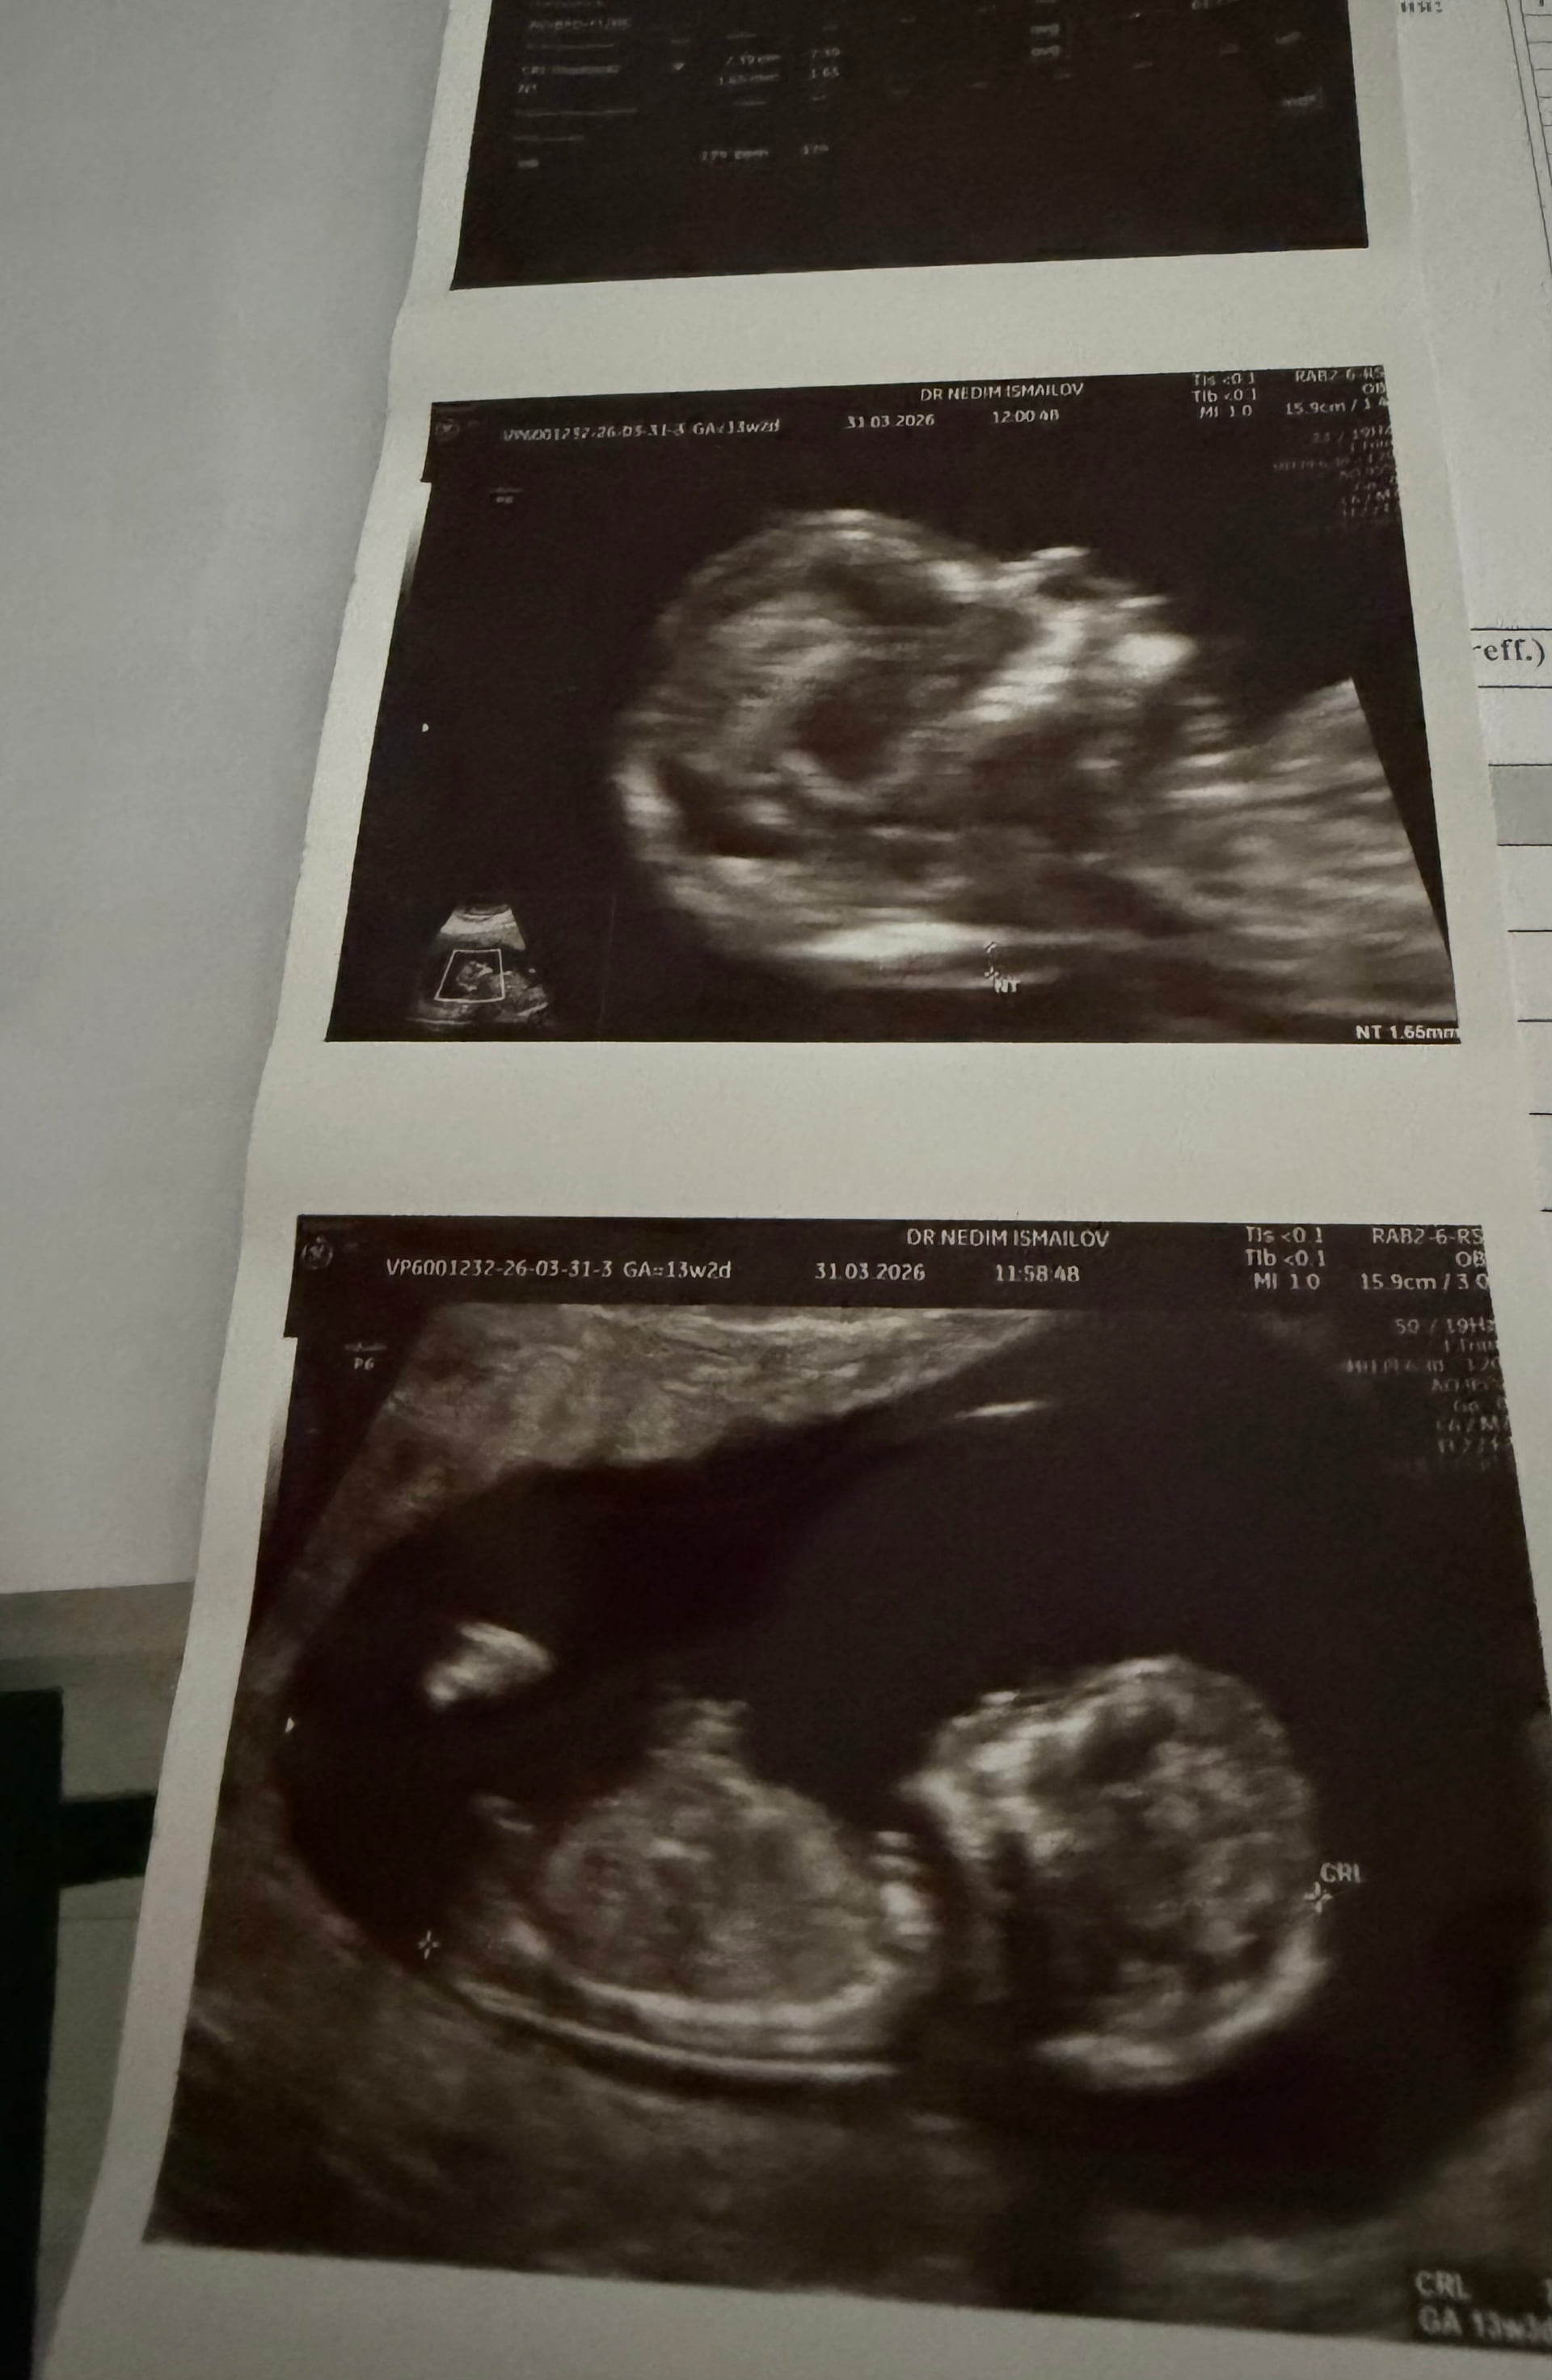

Canım çok net değil ama başka var mı yakin ve net tahmin edecek olursak erkek bebek gibi

Ters duruyor du zaten baş aşağı dı Doktor ne kız dedi ne erkek haftaya konuşuruz dedi kararsız kaldım dedim

Anladım baş aşağı durduğunu orda çıkıntı var o yüzden erkek gibi geldi kordon değil ise